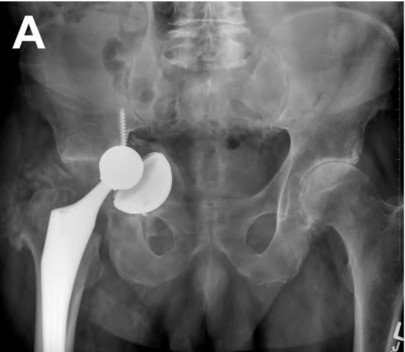

Question 23

A 75-year-old female sustains a fall 5 years after a cementless THA. Radiographs show a periprosthetic femur fracture occurring around the stem tip. Intraoperative assessment reveals the stem remains firmly fixed in the metaphysis, and the proximal bone stock is adequate. According to the Vancouver classification, what is the fracture type and the standard recommended treatment?

Explanation